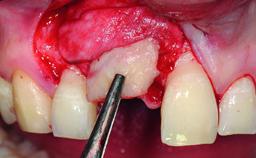

A 30-year-old patient presented at our clinic with a chief complaint of pain in her endodontically treated right maxillary central incisor (tooth 11) with a post-and-core and a fixed single crown. She had a very high lip line, a medium to thin soft-tissue phenotype, and a medium scalloped gingival contour. She also had high esthetic expectations because of her young age and beautiful smile. However, her expectations were realistic and she understood the risks of the treatment. At the initial clinical examination there was a slight mobility of tooth 11; no fistula was observed. The patient also had a single crown on the adjacent tooth 21. Both restorations were old and esthetically deficient. A digital periapical radiograph showed a very small periapical radiolucency, a thick intraradicular post, and no separation between root fragments.